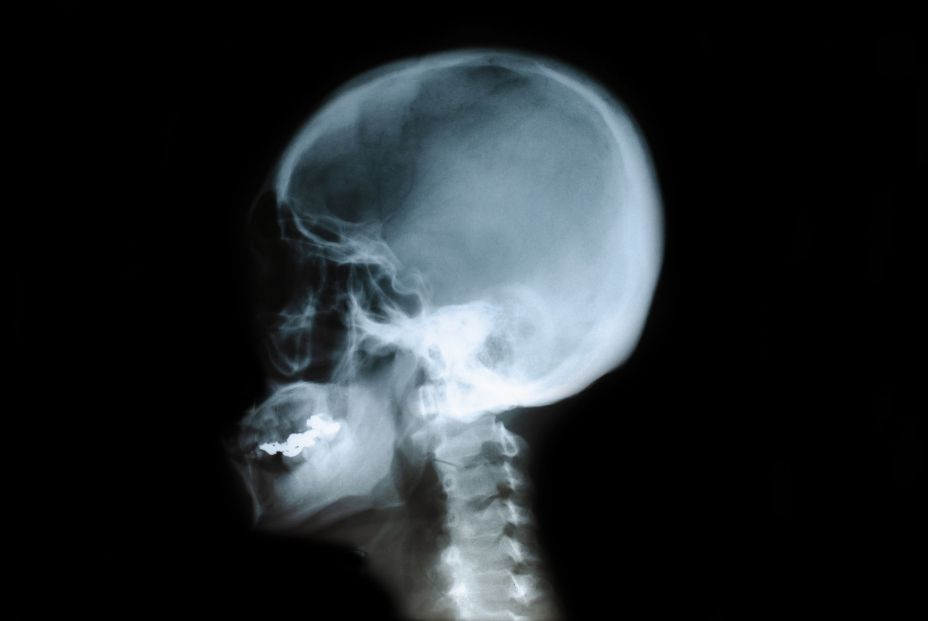

Los bebés y los ratones recién nacidos pueden curar de forma natural los daños en los huesos que forman la parte superior del cráneo, pero esta capacidad se pierde en los adultos. Sin embargo, ¿es posible recuperarla?

Los traumatismos, los defectos congénitos y la cirugía para tratar el cáncer u otras enfermedades son causas frecuentes de daños en el cráneo. A partir de los dos años de edad, estas lesiones no se curan por sí solas.